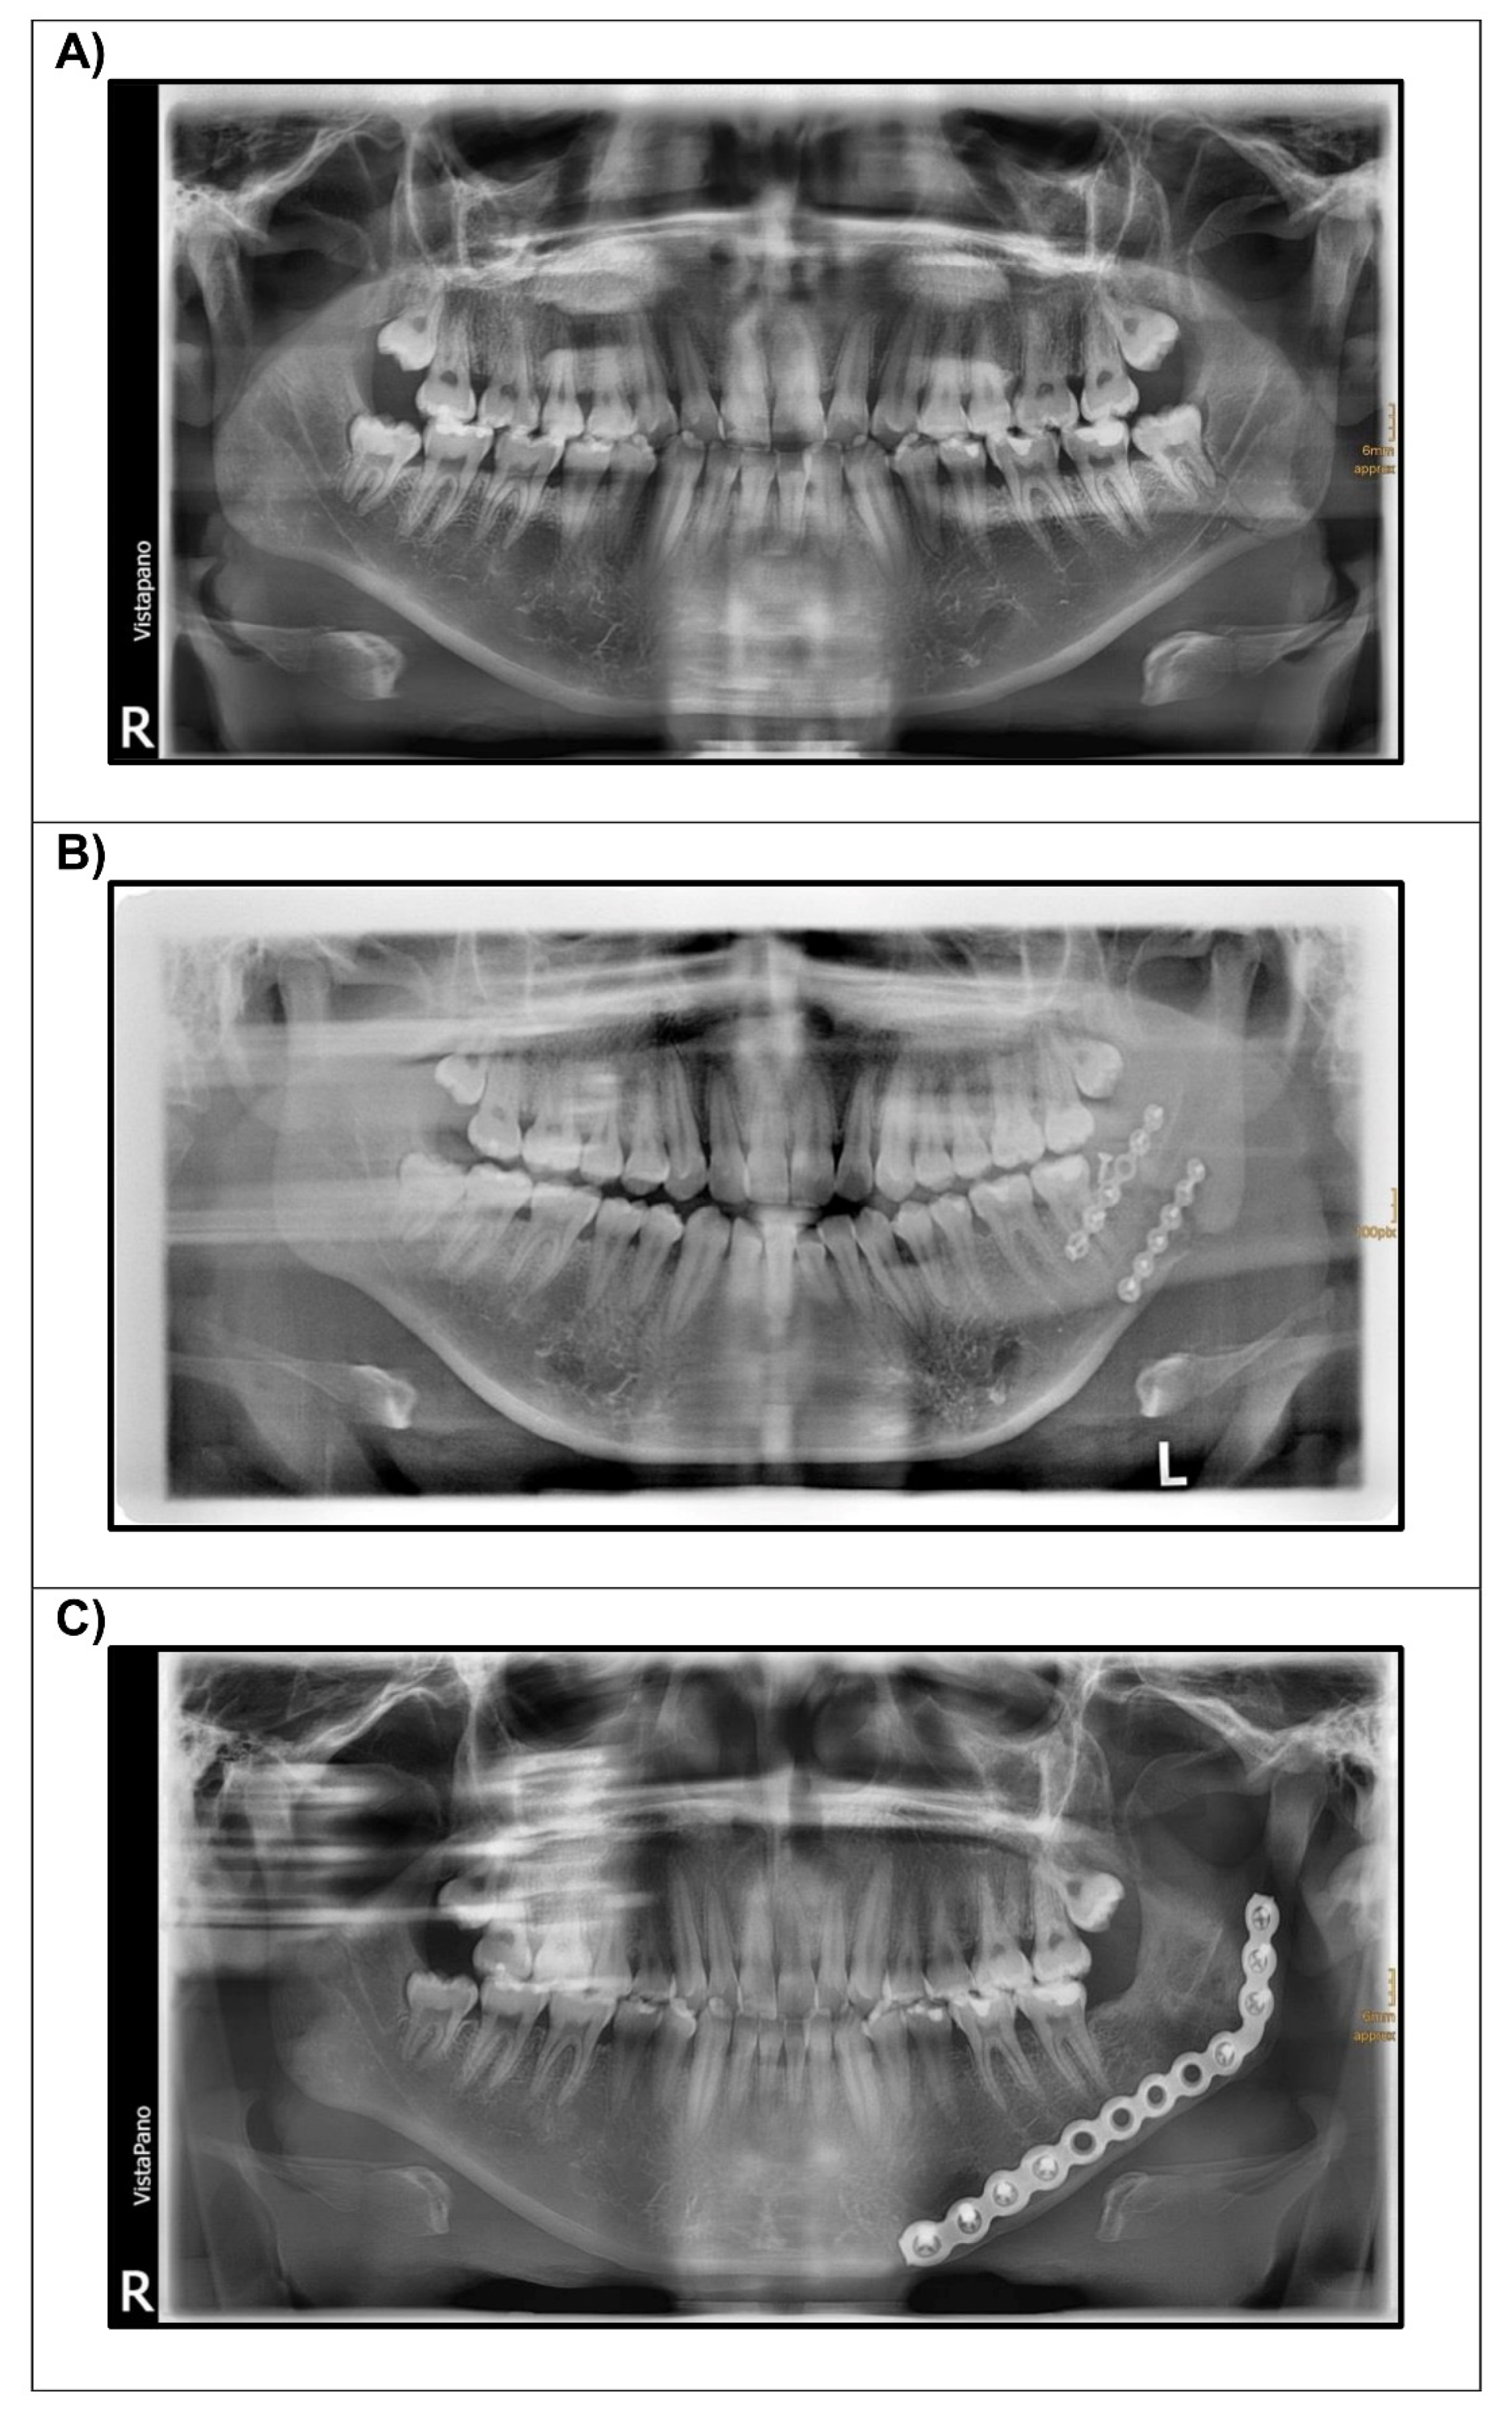

Feasibility of Implant Strain Measurement for Assessing Mandible Bone Regeneration

2. Materials and Methods

3. Results